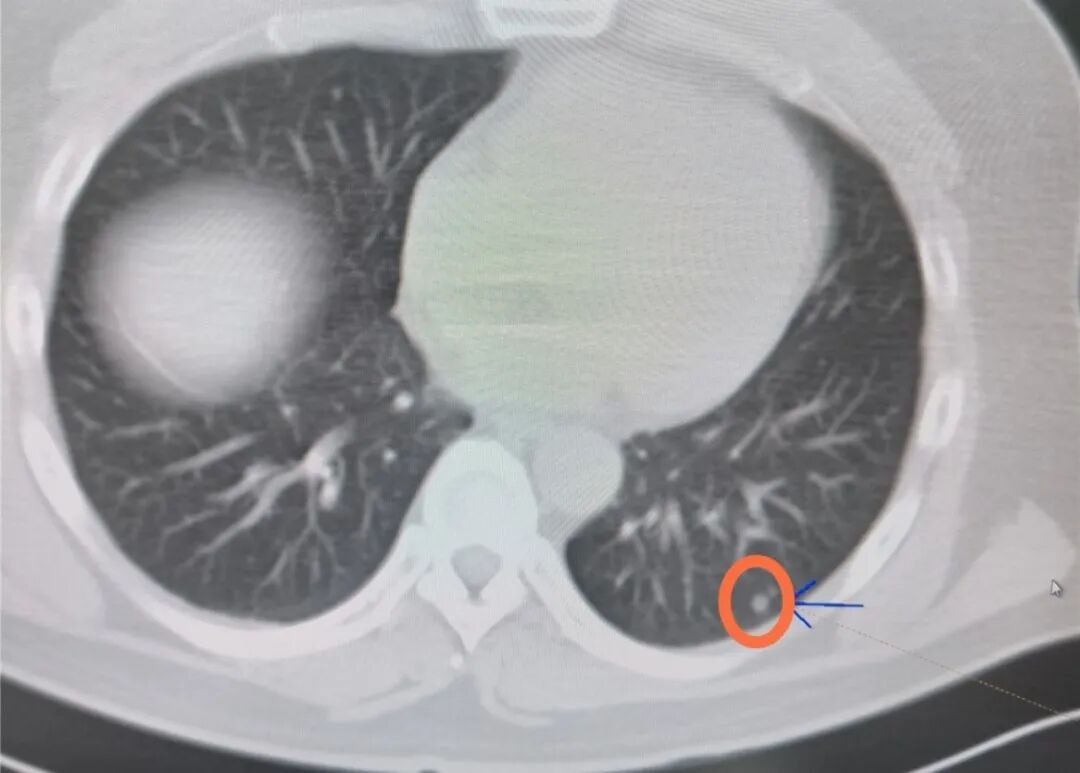

最要命的是

甲狀腺腫瘤已經出現了肺轉移